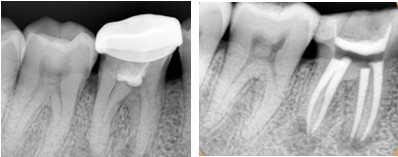

2、根管治疗按牙根收费

一般情况下我们的前牙只有1条牙根,而我们的磨牙则有3-4条牙根,因此治疗起来也会更麻烦更耗时间。